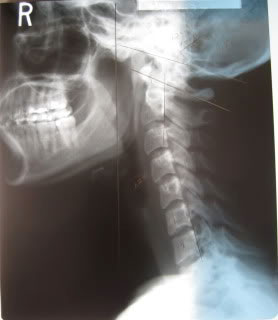

military-neck-xrayConditions related to the cervical spine continue to be of interest in the definition and treatment of fibromyalgia (FM). Several papers have been published regarding cervical stenosis (compression of the spinal cord in the neck), including a recent publication in the Pain Management journal about positional cervical cord compression and the correct MRI to diagnose the condition in FM patients. Another area of interest has to do with a straight neck phenomenon that in its-self can cause cervical cord compression and disability. The following article is meant as an educational piece concerning an ACR poster which offers more evidence of cervical neck compromise in a large cohort of FM patients.

The purpose of this study was to ascertain cervical spine abnormalities in FM patients. According to Dr. Katz, lordosis, or the natural curve of the neck, is missing in most FM patients. The straight neck in FM patients was based on calculating the Cobb angle, a standard radiographic measurement of lateral view x-rays of the cervical spine (C-1 through C-7).

The lordotic curve of cervical spine x-rays was measured by analyzing the Cobb angle in 138 consecutive patients in a rheumatology office practice. All the patients met the ACR criteria for FM and complained of moderate to severe neck pain. 23 additional patients with FM followed in the same medical practice had cervical radiographs reviewed visually by both a rheumatologist and an X-ray technician, but did not also have the Cobb angle measured (visual inspection group). The amount visual curvature was noted by each as 1 (straight neck), 2 slight lordotic curve) and3 (normal lordotic curve).

98 of 138 (71%) of the FM patients had a straight spine (Cobb angle less than 14 degrees). 24 of 138 (17%) of the FM patients had a small lordotic curve of the lateral view of the cervical spine x-rays (Cobb angle 14-18 degrees). 16 of 138 (12%) of the patients had a normal Cobb angle (more that 18 degrees) and a normal lordotic curve.

20 (87%) of 23 additional FM patients (visual inspection group) had a straight cervical spine by visual inspection. They had lost the normal lordotic curve. 3 (13%) of the FM patients had a slightly curved cervical spine. No FM patient had a normal cervical lordosis by visual inspection of lateral views of radiographs of the cervical spine. The Cobb angle in 10 rheumatic disease controls was 22.5 degrees and reported to be 26.8 degrees in healthy controls.

In conclusion, 88% of the FM patients in this study had a straight neck based on measuring the Cobb angle, and 90% had a straight neck by visualizing the lateral view of cervical spine x-rays. The cause of the straight cervical spine in FM is unknown. Speculation of the pathophysiology includes chronic muscle contraction and tightness of other soft tissues.